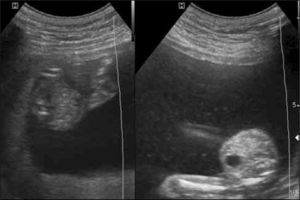

El diagnóstico se realiza bajo las 26 semanas mediante ecografía con la secuencia anhidramnios/polihidramnios donde el saco amniótico mayor mide >8cm (bajo 20 semanas) y >10cm entre las 20 y 25 semanas con vejiga fetal grande en el feto receptor y saco <2cm y ausencia de vejiga en el feto donante o stuck twin (figura 5). La clasificación más usada es la de Quintero y colaboradores (24) (tabla 1).